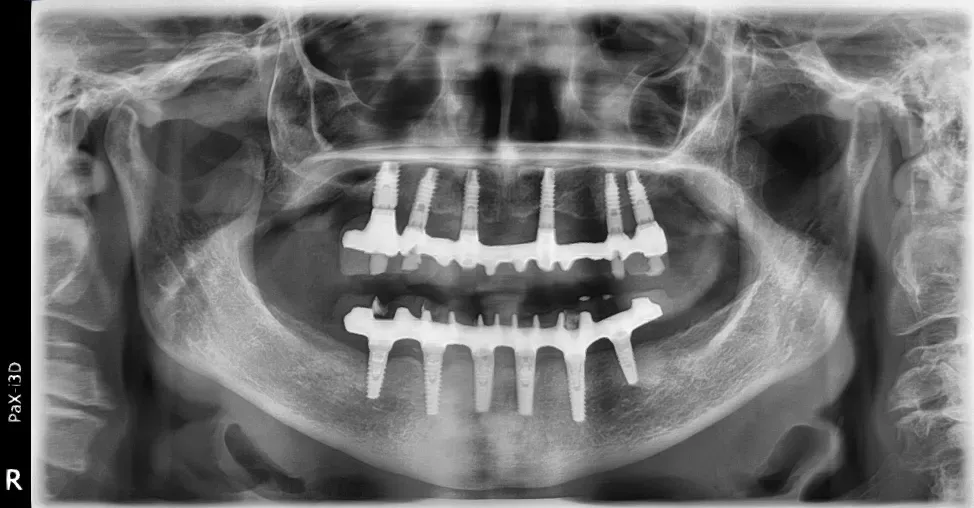

Le immagini radiografiche che seguono testimoniano alcune delle tante soluzioni tecniche che ho utilizzato per le arcate a carico immediato nel corso della mia carriera. Ogni caso presenta sfide diverse e richiede un approccio personalizzato.